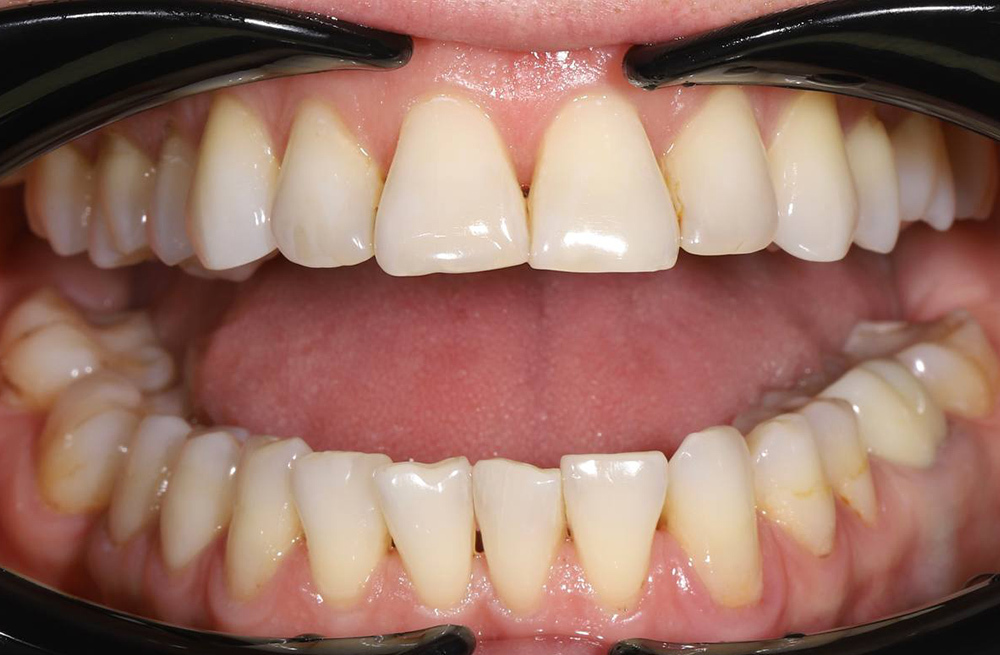

Примеры работ